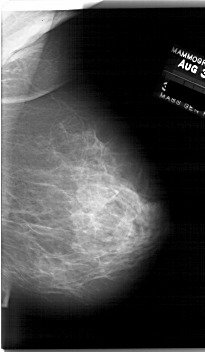

A_1761_1.RIGHT_MLO

RIGHT_MLO LINES 6676 PIXELS_PER_LINE 3886 BITS_PER_PIXEL 12 RESOLUTION 43.5 NON_OVERLAY